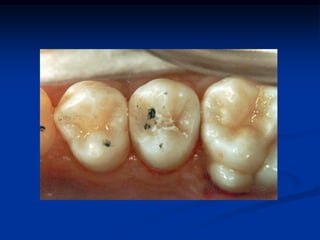

Selamento Oclusal

Alternativas para tratamento de

molares recém-erupcionados

   Acompanhamento clínico

   Acompanhamento clínico + escova unitufo

   Agentes quimioterápicos

   Vernizes de flúor e clorexidina

Técnica de Moldagem Oclusal

 Dentes Conóides

TÉCNICA DA MOLDAGEM OCLUSAL

É uma técnica restauradora que visa

reabilitar o mais próximo ao natural a

anatomia oclusal e-ou ocluso-proximal,

através da confecção de uma matriz ou

moldagem oclusal.

Objetivos

Minimizar as fases de acabamento

Reabilitar a anatomia natural

Indicação